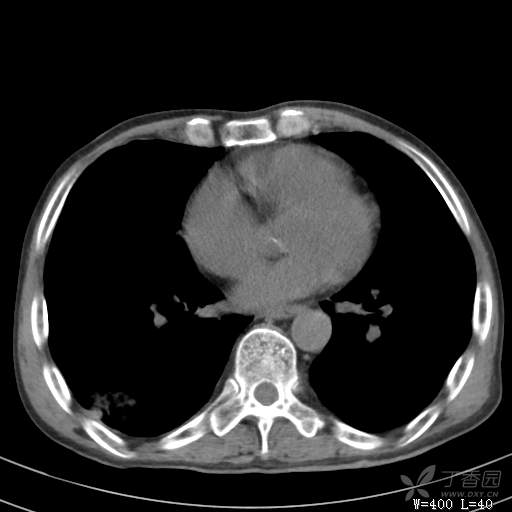

简要病史:主因发热伴腰背部疼痛2小时于2018-06-27,09:30 入院。患者无高血压,冠心病、糖尿病病史,无慢性咳喘史,不吸烟。否认食物药物过敏史。患者于入院前2小时出现发热,体温37.5℃,无咳嗽,咳痰,伴右侧腰背部疼痛,伴呕吐2次,呕吐物为黄绿色胆汁,大便2次,为稀便,无咯血,无胸闷、憋气,无鼻塞、流涕,无尿频、尿急、尿痛,就诊于我院,我院急诊查:上腹部CT:右肾结石,右下肺感染性疾病可考虑,血常规WBC13.54*109/L,GR%45.8%,急诊以“发热待查:肺感染?”收入院。

辅助检查:上腹部CT:右肾结石,右下肺感染性疾病可考虑,血常规:WBC13.54*109/L,GR%45.8%,。心肌酶示:谷草转氨酶12U/L,乳酸脱氢酶328U/L,肌酸激酶20U/L,肌酸激酶同工酶7U/L,α-羟丁酸脱氢酶277U/L,查凝血常规示:凝血酶原时间12.5秒,国际标准化比值1.07,活化部分凝血酶原时间32.6秒,纤维蛋白原浓度1.77g/L,凝血酶时间15.6秒。

临床诊断:1.腰背部疼痛原因待查:1.肺炎?2.泌尿系结石?。